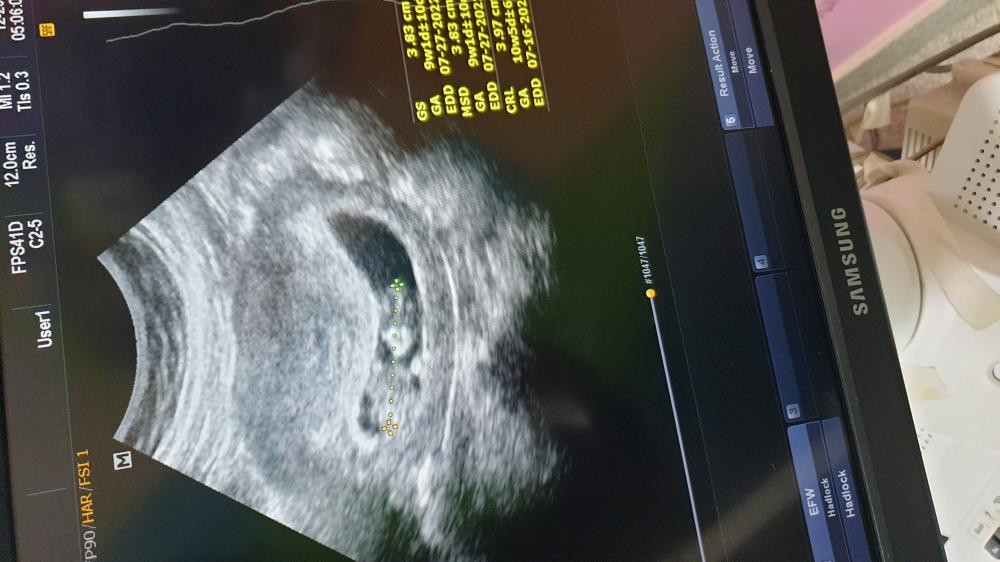

مساء الخير بنات انا عضوه جديده معاكم الاسبوع 12 حسبتي على 10 / 7 الولاده ان شاء الله بس في احتمال ولاده مبكره بس ان شاء الله خير 🌺🤍

على حسب الدوره ولادتي ب١٤ والسونار يعطي ٢٧ استغربت